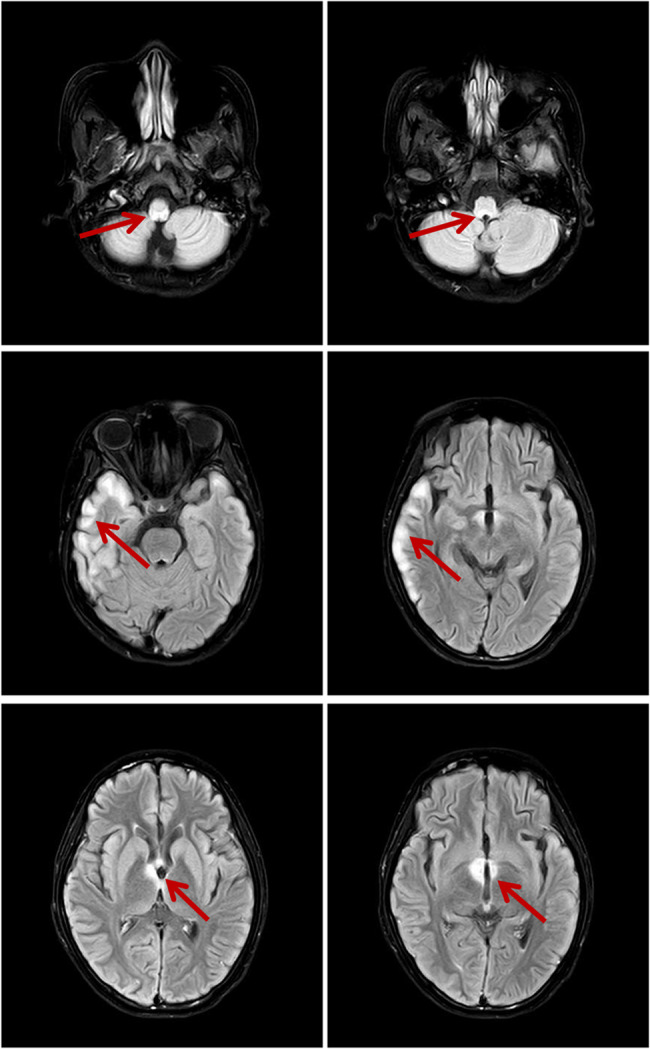

Mycoplasma pneumoniae infection and concurrent aquaporin-4-positive neuromyelitis optica spectrum disorder: a case report and literature review.